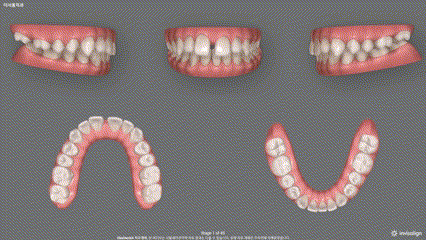

【 결과 】

앞니 벌어짐 은

반년이 채 걸리지 않아서 닫혀버렸습니다.

약 1년 반이 흐르고

2급 부정교합 및 하악 전치부 총생이

말끔히 없어졌네요.

환자께서도 너무 마음에 든다는

말씀을 하셨는데요.

성공적으로 앞니 벌어짐 치료를

마칠 수 있었습니다.

치료기간 2020.02.11 ~ 2021.07.12